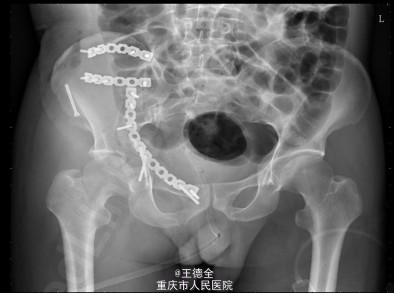

患者男性,51岁,因“高坠伤致左腰部及右髋部疼痛伴活动障碍3天”入院。急性痛苦面容,神志清楚,平车送入病房,右髋部软组织稍肿胀,局部皮肤完整,未见明显皮疹,挫擦伤及出血点.右股骨髁上骨牵引在位,左腰椎伴明显压痛,骨盆挤压实验阳性,可扪及骨擦音,骨擦感.双下肢感觉,活动,血循良好,足背动脉搏动好;右踝关节主动活动受限,被动活动正常。右侧各足趾背伸、跖屈活动正常,其余各关节活动正常。骨盆X线片示:右侧髂骨、髋臼、双侧耻骨上支、右侧耻骨下支多发骨折,左侧髂骨翼骨折,骨盆出入口右侧份形态失常。 初步诊断:右髋臼粉碎性骨折(Judet X 型) 诊疗计划:完善双下肢静脉彩超等检查;给予预防深静脉血栓、骨牵引治疗;给予止痛等对症支持治疗;密切观察病情变化,根据病情及时处理。